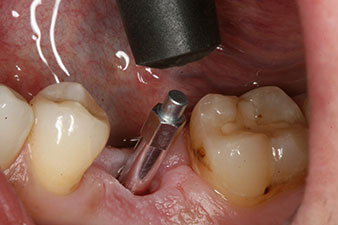

SmartPeg

Fig. 4: SmartPeg measuring posts screwed on to measure the implant stability quotients with the integrated W&H Osstell ISQ module.

The torque used for the machine-driven placement was 43 Ncm. In addition, after screwing a measuring post (SmartPeg) specially matched to the implant, the ISQ value was measured with the probe of the W&H Osstell ISQ module.